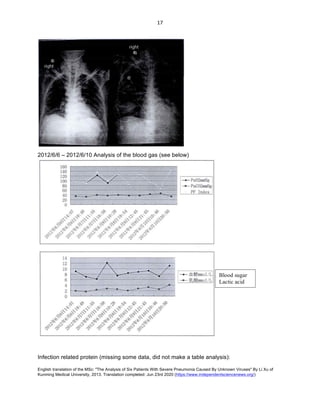

2012/4/28 – 2012/8/13 Analysis of blood gas (see below):

2012/4/25 – 2012/8/13 related infected protein (see below)

Oxygenation

Index

Blood	sugar

Lactic	Acid